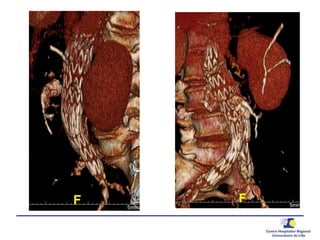

TYPE 2 – hypogastrique

TYPE 2 – AMI